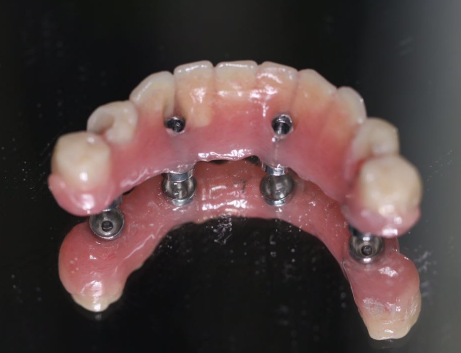

All-on-4全/半口種植技術(shù)突破傳統(tǒng)種植牙技術(shù),只需種入4顆(全口8顆)種植體,就可以恢復(fù)全/半口牙的咀嚼功能,在患者口腔狀態(tài)符合的條件下,可以實(shí)現(xiàn)當(dāng)天種牙,當(dāng)天戴牙冠吃東西。

2、單頜植入4個植體,遠(yuǎn)中兩個傾斜,上頜避開上頜竇前壁,下頜避開頦孔和下頜神經(jīng)。

4、最終修復(fù)到第六個恒牙。